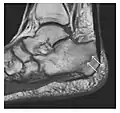

Occult osseous injuries may result from a direct blow to the bone by compressive forces of adjacent bones against one another or by traction forces during an avulsion injury. Lesions in the tibial plateau, hip, ankle, and wrist are often missed. In a tibial plateau fracture, any disruption of the posterior and anterior cortical rims of the plateau should be sought. Impaction of subchondral bone will appear as an increased sclerosis of the subchondral bone (Figure 1). In the hip, posterior acetabular fractures also present subtle radiographic findings. The acetabular lines should then be carefully examined keeping in mind that the posterior rim, which is harder to see on X-rays, is more frequently fractured than the anterior rim (Figure 2). In the wrist, detection of carpal bone fractures is often challenging, with up to 18% of scaphoid fractures radiographically occult. Carpal fractures, especially the scaphoid, are associated with the risk of avascular necrosis. In apparently normal wrist radiographs from symptomatic patients, if there is history of a fall on an outstretched hand with pain in the anatomic snuffbox, suggesting scaphoid injury, the initial examination with posteroanterior, lateral, and pronation oblique views must be complemented by other specific views such as supination oblique and the "scaphoid" view A careful examination of cortices for evidence of discontinuity or offset and cancellous bone for lucency is necessary (Figure 3).[1]

Figure 3: A 26-year-old man presenting with wrist pain after being assaulted. (a) Initial anteroposterior radiograph shows a subtle linear lucency within the scaphoid extending to the scaphocapitate articular surface that was overlooked (arrow). (b) Initial "scaphoid" view was negative. (c) Followup anteroposterior radiographs, 12 days later, shows obvious scaphoid fracture (arrows).[1]